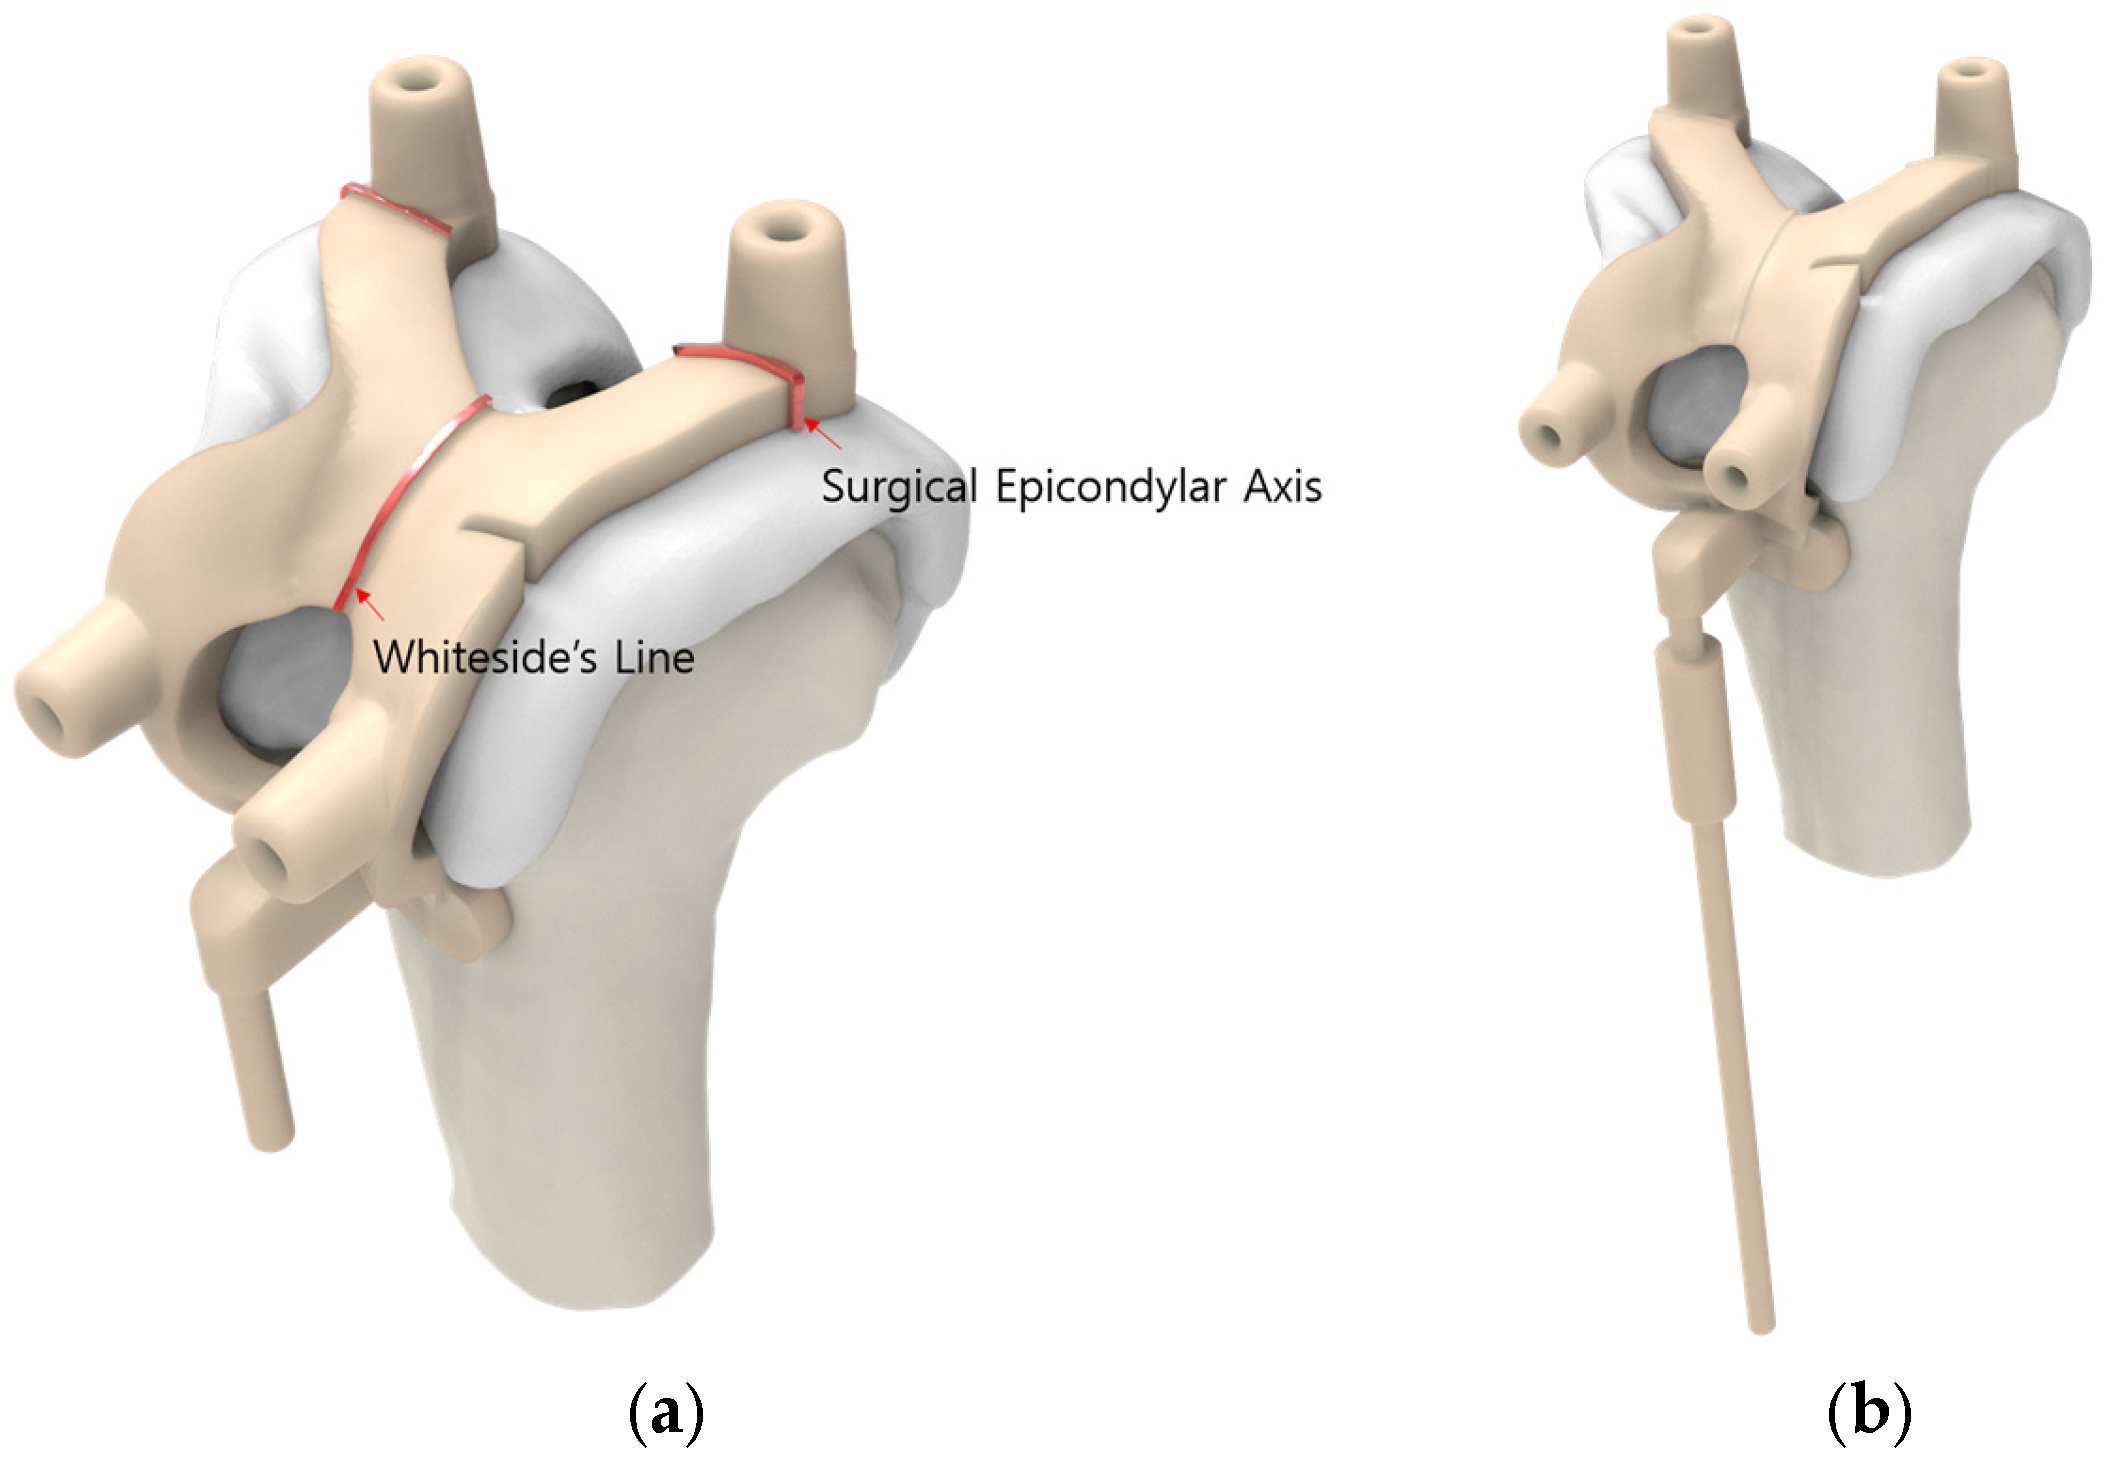

2.2. Pre-Planning and PSI Design Methods